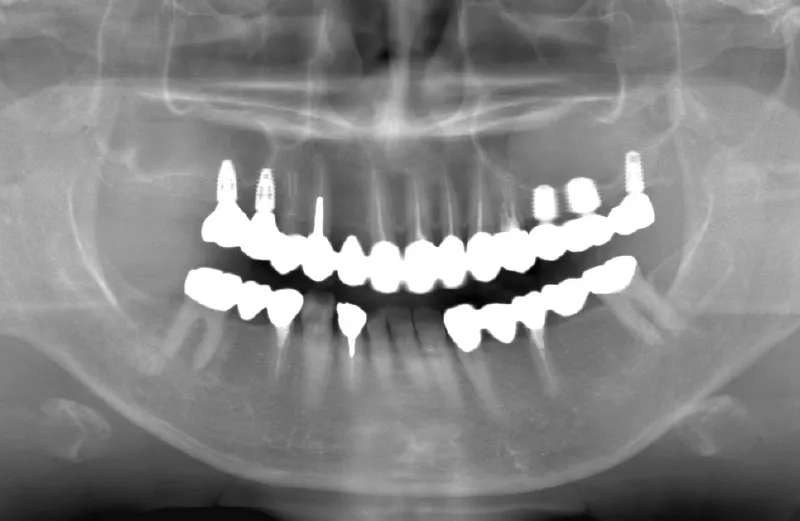

メガジェンオペ症例

メガジェンオペの症例紹介01

治療前

治療後

| 主訴 | 上入れ歯は以前に入れたことがあるが違和感が強く入れられなかったのでインプラントで治療して欲しい。 他院では上顎洞までの垂直骨量が1~3mm程度しかないのでサイナスリフトが必須であり、インプラント治療で歯が入るまでに1年以上かかると言われたのでセカンドオピニオンを希望で来院。 |

|---|---|

| 治療期間 | 2.5ヶ月で仮歯が入り、 4ヶ月で最終補綴物が入って終了。 |

| 費用 | 約1,500,000円 |

| 治療内容 | エクストラワイドショートインプラントを埋入し、上顎洞を移植材を用いずに挙上しインプラントを埋入した。約2.5ヶ月で仮歯を装着し、様々な機能面に問題がないことを確認し4ヶ月で最終補綴物を装着して終了した。 |

| 治療のリスク | インプラント埋入オペ時に術者が上顎洞内にインプラントを迷入させる可能性がある。これは術者が技術的に熟練していれば防ぐことが可能。 |